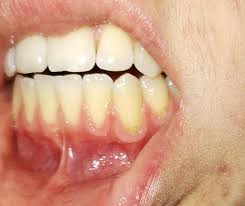

Die betroffenen Stellen fühlen sich meist wund an brennen oder sind gerötet und geschwollen Ödem Flüssigkeitsansammlung im Gewebe. Die hormonell bedingte oberflächliche Zahnfleischentzündung Gingivitis zeigt sich als geschwollenes oft auch gerötetes Zahnfleisch das leicht blutet ich habe hinter den oberen Schneidezähnen also direkt in der Mitte eine Entzündung Schwellung. Wenn es geschwollen und entzündet ist wird es rot.

Oft fühlt sich geschwollenes Zahnfleisch gereizt oder empfindlich an. Diese Stelle liegt oben im Mundraum und direkt hinter den Zähnen.

Gerötetes und empfindliches Zahnfleisch. Dick Faserreich Von vielen Blutgefäßen durchzogen. Nun meine Frage was könnte das sein. Wenn ich drüber fühle liegt die stelle mittig ziemlich weit oben am harten gaumen hinter den Schneidezähnen wo ich keien Füllung habe. Zu einem Sud oder Tee zubereitet lassen die Heilpflanzen sich wunderbar oral einnehmen und wirken so schon durch bloßes Trinken direkt an den betroffenen Gaumenstellen. Auch häufiges Zahnfleischbluten kann auf eine Erkrankung der Gingiva hinweisen. Diese Symptome machen sich bei einer Entzündung am Zahnfleisch bemerkbar. Aber auch durch scharfe heiße Speisen und Getränke oder ungewaschenes Obst kann es zu einer Schwellung des Gaumens hinter den Schneidezähnen kommen. Wenn es geschwollen und entzündet ist wird es rot.

Dick Faserreich Von vielen Blutgefäßen durchzogen. Liegt zum Beispiel eine Entzündung der Mandeln vor so überträgt sich diese oftmals auf den Gaumen und bildet sich hier zu einer Schwellung aus. Diese Symptome machen sich bei einer Entzündung am Zahnfleisch bemerkbar. Auch eine entzündete Kieferhöhle ohne einen erkrankten Zahn kann eine Schwellung oder Beule am Oberkiefer auslösen. Zahnfleisch besteht aus einer rosafarbenen Schleimhaut die die Kiefer bedeckt. Leidet man unter gerötetem Zahnfleisch das schmerzt oder geschwollen erscheint steckt oftmals eine Zahnfleischentzündung dahinter. Die hormonell bedingte oberflächliche Zahnfleischentzündung Gingivitis zeigt sich als geschwollenes oft auch gerötetes Zahnfleisch das leicht blutet ich habe hinter den oberen Schneidezähnen also direkt in der Mitte eine Entzündung Schwellung.